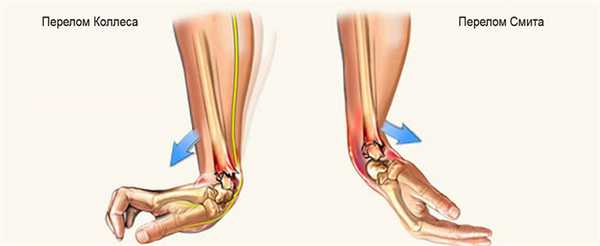

- омы. Особенно часто травмируется лучевая кость. Существует два вида перелома лучевой кости в лучезапястном суставе:

- Перелом Смита (сгибательный перелом). Причиной травмы служит падение на вытянутую руку, на ее тыльную сторону. Кость ломается и при этом происходит смещение костных отломков в сторону ладони.

- Перелом Коллеса (разгибательный перелом). Повреждение случается при падении человека на ладонь, наблюдается смещение костных отломков в сторону большого пальца и тыльной поверхности кисти.